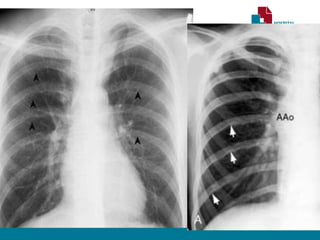

RADIOGRAFIA TORÁCICA

• Sinal de Roesler:

• Erosões bilaterais na borda inferior dos arcos costais (3ª - 9ª).

• Sinal do “ 3 invertido”

• Dilatação Subclávia E.

• Segmento estenótico aparece como um entalhe

• Dilatação pós estenótica.

• Contorno do arco aórtico apagado.